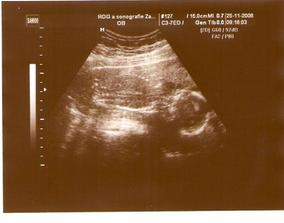

25.11.08 utz v pořádku odpovídáme 19tt+6

13.12.08 3D UTZ, nedopadl moc dobře, malá si pořád zakrývala obličejík, vyplazovala jazyk, zamávala a pak už s náma nehodlala spolupracovat, navíc si nejsou jistý pohlavím, kvůli pupeční šňůře co měla mezi nožičkama, takže kdo ví co na nás v dubnu nakonec vykoukne🙂